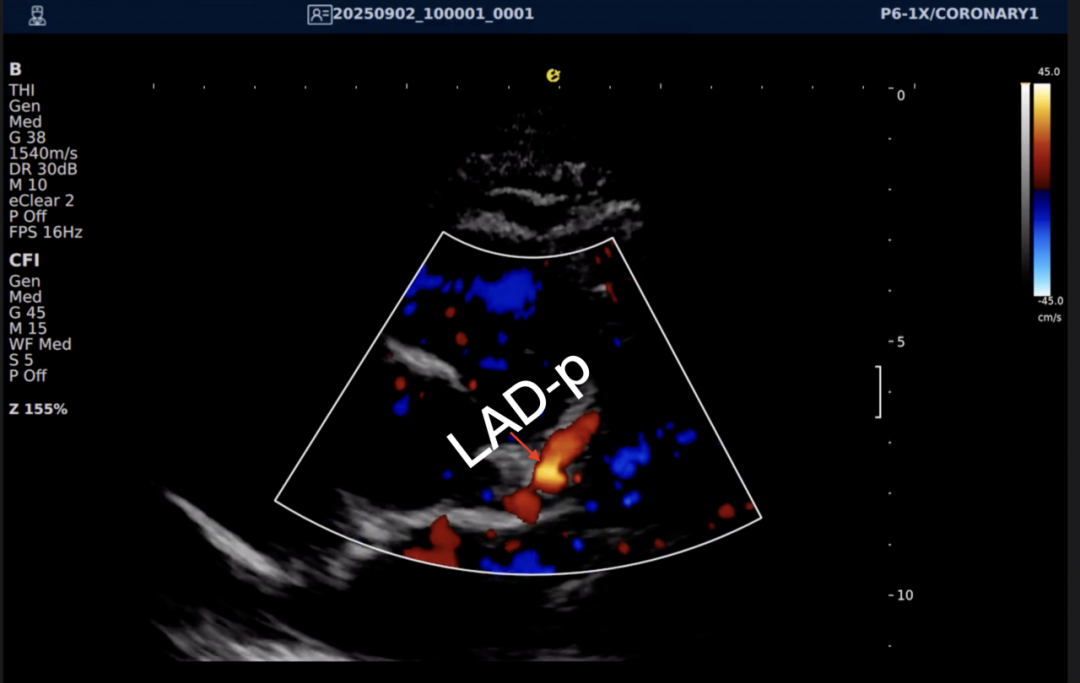

以下为逸超医疗(ESI)设备采集的冠脉图像,清晰展示了其在二维成像、彩色多普勒及频谱多普勒方面的表现:

左右滑动查看更多

心脏冠脉超声

一例胸闷患者,临床采用无创冠脉超声作为初步评估手段,检查中发现:

彩色多普勒:敏感捕捉到局部血流加速现象;频谱多普勒:测得峰值血流速度明显升高,频谱形态异常。

基于超声提示的异常发现,临床为患者安排了冠脉CTA检查,结果显示前降支近段存在约45%狭窄,与超声提示的血流动力学改变高度一致。

这一病例体现了冠脉超声作为初筛工具的重要价值:它能够无创、实时地评估冠脉血流动力学状态,为后续是否需要进一步影像检查提供重要参考。超声与CTA的协同应用,既能评估结构变化,又能反映功能状态,为临床诊断提供了更全面的信息。